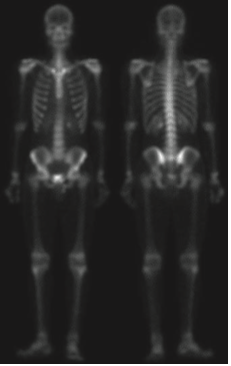

그 결과 영상 내의 강한 엣지들이 더 많이 남아있으며 노이즈는 라플라시안만 활용한 것에 비해서 더 줄어든것을 관찰할 수 있습니다. 이제 강한 엣지 영상을 샤프닝하는 데 사용해주면 됩니다.

실제로 일반적인 샤프닝 영상에 비해서 훨씬 깔끔한 영상을 얻은 것을 볼 수 있습니다. 하지만 여전히 밝기값이 낮기 때문에 마지막으로 거듭제곱-법칙 변환을 적용해여 아래의 최종 영상을 얻을 수 있습니다.